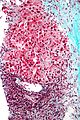

Hepatocellular carcinoma superimposed on cirrhosis in a 60 year old man. A. Dark tumor, sometimes with separate cords visible at low power (black arrow), contrasts with lightly colored regenerative nodules (green arrows) within fibrotic bands. B. Regenerative nodules are separated by a band with proliferated bile ducts, whose orientation, lacking haphazard spread, bespeaks a benign process. C. Reticulin of regenerative nodule shows two cell thick cords lacking orientation, disrupted without reason, aggregated and, at left, slighely dispersed. D. Hepatocellular carcinoma shows darker cytoplasm and more nuclei per square mm than regenerative nodules. Note the many acini, also a good sign of cancer. E. Reticulin fibers have disappeared, leaving cords with 6 or more nuclei thick in places. F. PAS D stain shows benign proliferated bile ducts, whose orientation from lower left to upper right deprives the proliferation of the haphazard nature of a cholangiocarcinoma. G. PAS-D shows the cytoplasmic digestion of glycogen in a hepatocellular carcinoma, a helpful hint at times. Note the finger like cords, the mitosis (black arrow), and the occasional acinar lumens (red arrows). H. PAS D of regenerative nodule contrasts with the image of the hepatocellular carcinoma.